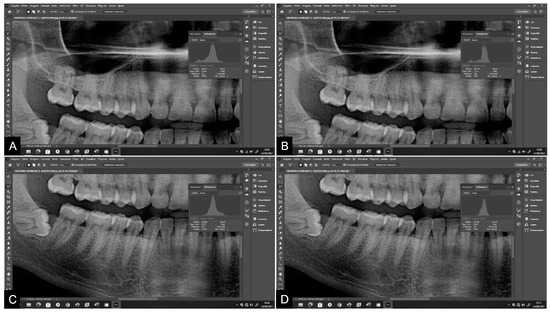

| Measure 1 | Measure 2 | p * | ICC (CI 95%) | |

|---|---|---|---|---|

| Pan T13/23 | ||||

| Tooth area | 19,013 | 18,762 | 0.579 | 0.999 |

| Pulp area | 2110 | 2081 | 0.606 | 0.997 |

| Peri T13/23 | ||||

| Tooth area | 22,501 | 22,686 | 0.643 | 0.990 |

| Pulp area | 2523 | 2552 | 0.239 | 0.996 |

| Pan T35/45 | ||||

| Tooth area | 15,139 | 15,610 | 0.717 | 0.999 |

| Pulp area | 1623 | 1619 | 0.116 | 0.998 |

| Peri T35/45 | ||||

| Tooth area | 15,656 | 15,540 | 0.055 | 0.999 |

| Pulp area | 1534 | 1449 | 0.557 | 0.995 |